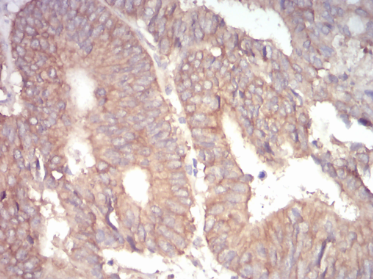

IHC    1/200 - 1/1000